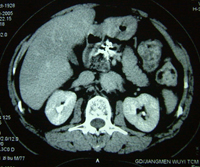

黃先生告訴記者:2004年7月初,他大便次數增多,腹部隱隱不適,去江門市人民醫院檢查,做B超和CT,發現胰腺腫癌。突然的打擊幾乎讓他精神崩潰。黃先生的太太是護士,對胰腺癌的嚴重性早有所聞。有醫生勸黃先生接受手術,但全家反對,一方面黃先生年事已高,另一方面他們了解胰腺癌能切除者微乎其微。一位鄰居告訴他們:廣州復大腫瘤醫院有不開刀的冷凍治療,對肝癌、肺癌等許多腫瘤有良好效果。7月14日,夫妻倆帶著簡單的行李,直奔廣州,當日住進復大腫瘤醫院。牛立誌博士等醫務人員給黃先生作了詳細檢查,作了腫瘤活檢,確診為胰腺囊腺癌。7月16日,黃先生接受了冷凍加125-碘粒子植入治療。醫生在CT引導下,作腹部穿刺,不開刀,將細針直接插入胰腺腫瘤內,先冷凍,再植入125碘粒子20粒。第二天,黃先生下地行走;第三天,恢復正常飲食;第八天,出院回家。三年來,除腿關節有點老年退化性變性外,他生活完全正常,無疼痛,食欲好,睡得香,每天散步半小時。CT復查顯示:胰內腫瘤消失。

黃先生胰腺癌治療前後CT:A 治療前,B 治療後3個月,C 治療後12個月